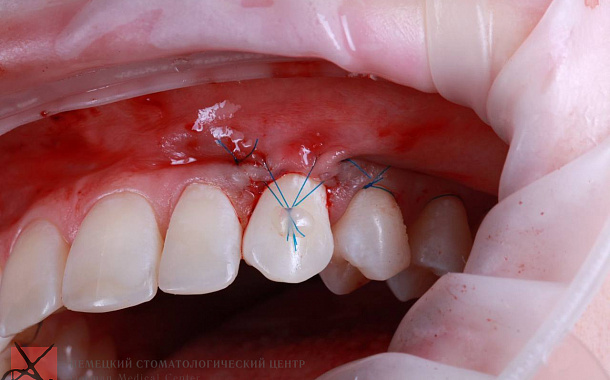

Применение Indiba после стоматологических процедур, таких как удаление зубов, костная пластика и имплантация, обеспечивает ряд значительных преимуществ:

- Улучшение приживаемости имплантатов: усиление кровоснабжения в области имплантации способствует лучшей интеграции имплантата с костной тканью.

В Москве аппарат Indiba представлен лишь в нескольких ведущих стоматологических клиниках, что делает эту процедуру эксклюзивной и высокотехнологичной опцией для пациентов, стремящихся к наиболее эффективному и комфортному восстановлению после стоматологических вмешательств. Наличие Indiba в Немецком Стоматологическом Центре подчеркивает нашу приверженность инновациям и стремление предоставить пациентам самые передовые методы лечения.